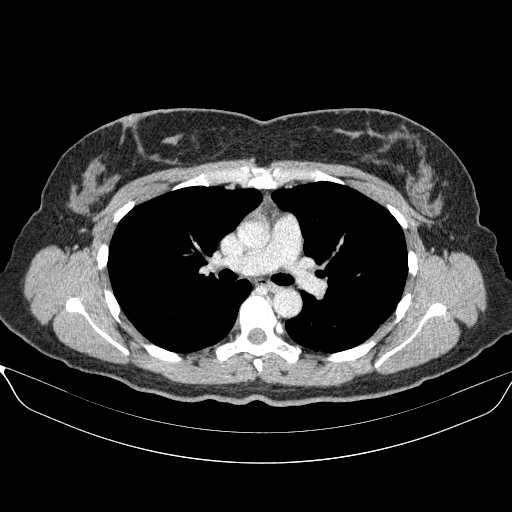

Generated VENOUS CT scan (A→B translation)

Full window (WL 1023.5, WW 4095 β†’ Low βˆ’1024, High +3071)

Lung window (WL -600, WW 1500 β†’ Low βˆ’1350, High +150)

Mediastinum window (WL 40, WW 400 β†’ Low βˆ’160, High +240)